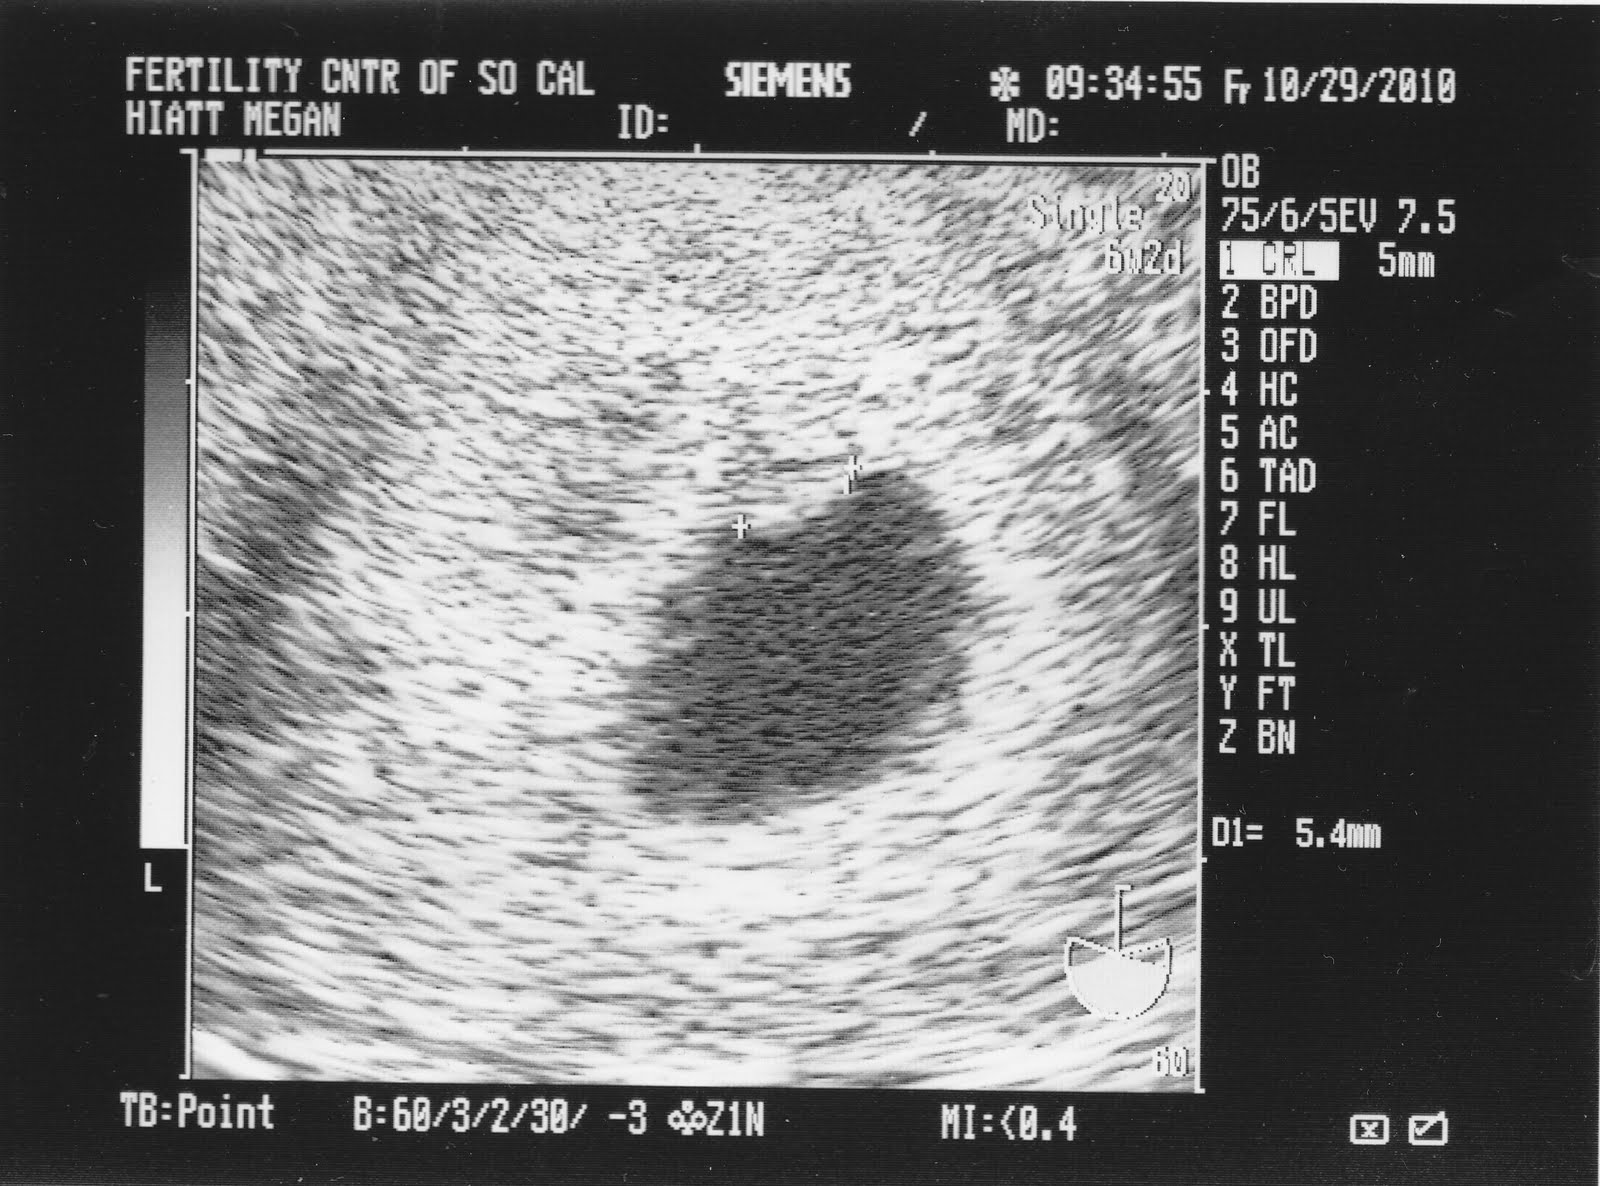

Next ultrasound on October 29 at 6 weeks shows a cute little peanut.